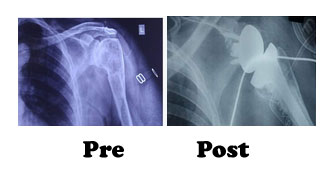

In reverse shoulder, we reverse the normal anatomy of the shoulder so that normal active muscles surrounding the joint will help in its complete range of motion.

Our experience: In 2017 we have started reverse shoulder replacement in a hospital in Amritsar.

The short term results of these patients are very encouraging and persuade us to promote it more for greater benefit of the patients suffering for irreparable losses to the shoulder joint.